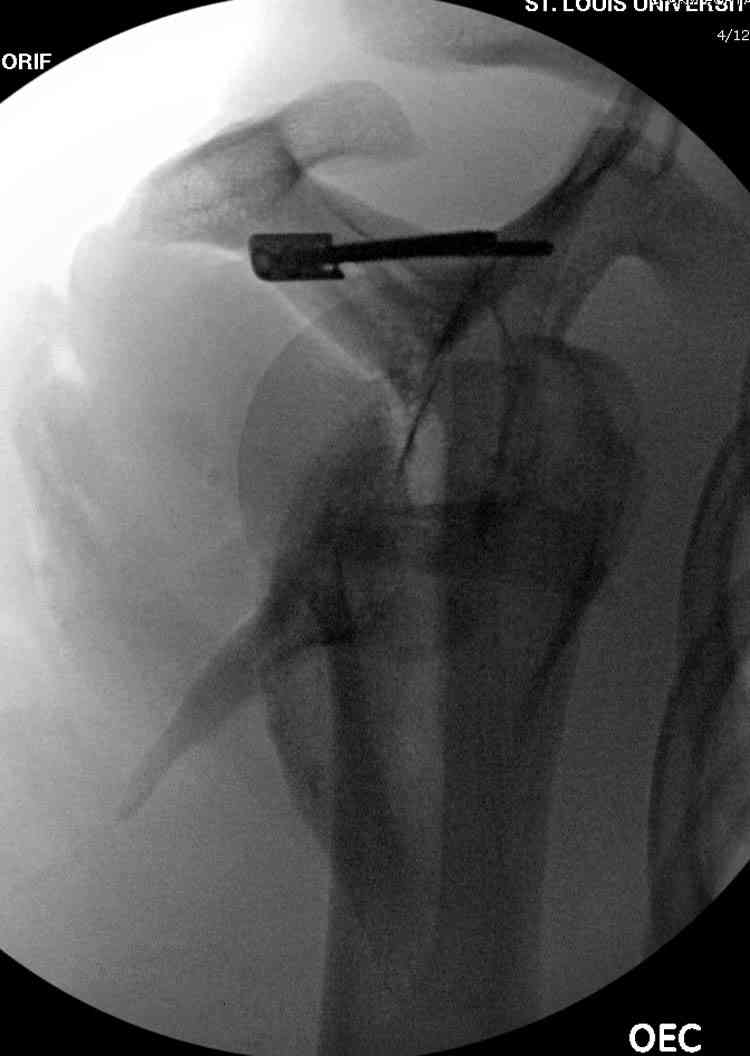

На снимке (№6 компьютерная томограмма и 3D №7) перелом клювовидного отростка.

Передним дельтопекторальным Bankart доступом намного легче провести фиксация отростка, но тогда репозиция и фиксация колонн затрудняется, поэтому был применен стандартный Judet задний доступ.

Репозицию смогли сделать пальцами через щель между

шейкой и телом лопатки (последний 3D снимок)